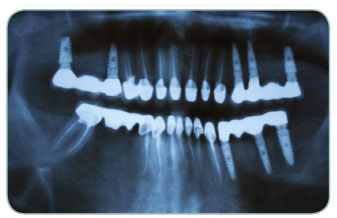

Our patient had severe problems and he was about to loose all of his teeths in the following one or two years. We have extracted all teeth and replaced 7 Implants per upper and lower part of the mouth and after one and a half months healing period, we have replaced the fixed porcelain prosthetics. During the healing period our patient was able to continue his normal life through the temporary prosthetis that we applied. Total treatment period was only three and half a months!